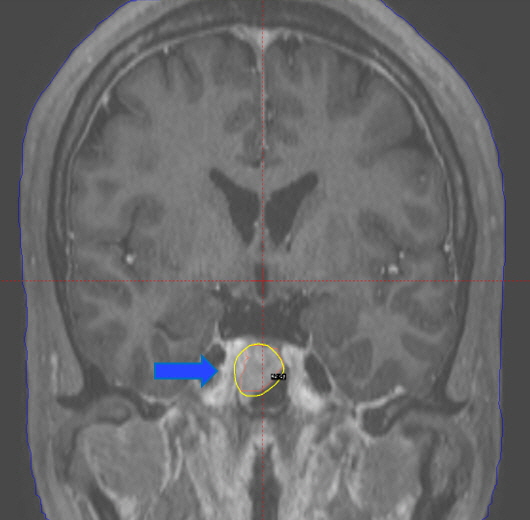

뇌하수체종양 방사선 수술 전 이미지

방사선 수술 전